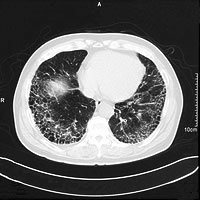

慢性呼吸不全になるもうひとつの代表的な病気として肺線維症があります。別名を「間質性肺炎」といい、病 気が進むと「肺線維症」と呼ばれます。肺胞をつなぎ合わせている間質に炎症が起こって分厚くなり、酸素を取り入れる血管までの距離が遠くなるため、呼吸を しても酸素が体の中に入っていきにくくなる病気です(図4)。

炎症が、肺のごく一部にとどまっているときは自覚症状はありませんが、広い範囲にわたると歩行などの作業によって強い呼吸困難があらわれます。胸部レントゲンやCTでは肺の炎症の部分が白く網目のように見えます(写真(5)(6))。

| 図5 肺線維症の肺のレントゲン | 図6 肺線維症の肺のCT |

| 【肺線維症】両肺の中~下を中心に網目状に見える陰影が炎症部分(5)。肺の周辺に線維化が起こり、蜂の巣のように見える(6)。 | |